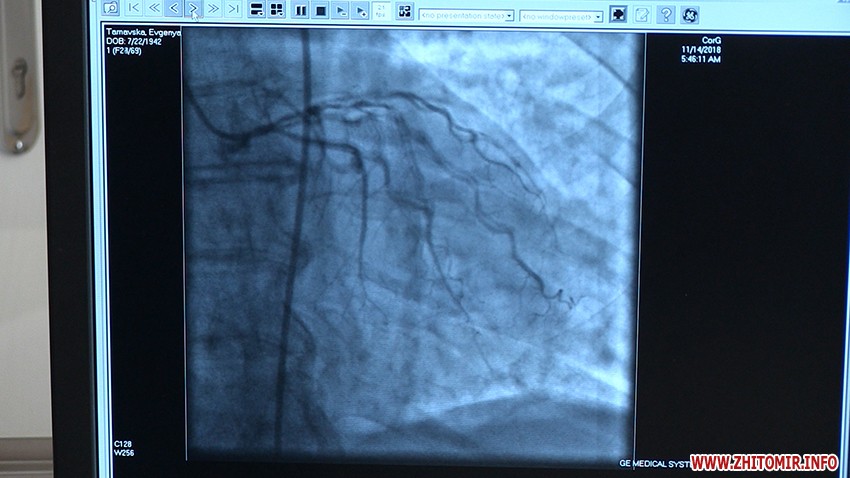

У Житомирській обласній клінічній лікарні імені Олександра Гербачевського 14 червня презентували відремонтовану операційну з новим ангіографом. Відтепер у лікарні працюватиме два таких апарати, що допомагають розпізнавати та реагувати на зміни в судинах та тканинах організму.

«Це дороговартісне і високотехнологічне обладнання і, найголовніше, що ми отримали те обладнання, яке хотіли та просили, щоб надавати допомогу не тільки пацієнтам з патологією серця, а й по інших системах і органах. Завдяки цьому апарату ми збільшуємо кількість пацієнтів, яких ми можемо пролікувати від інфаркту міокарду. Цей апарат дає можливість лікувати не тільки судини серця, а й головного мозку. Наступний напрямок - електрофізіологічна лабораторія, їх в Україні всього дві чи три. Це надзвичайно технологічний метод лікування пацієнтів, які мають порушення серцевого ритму. Також лікування доброякісних та злоякісних пухлин, стентування судин, в основному, нижніх кінцівок», - розповідає головний лікар обласної клінічної лікарні ім. Гербачевського Богдан Леськів.

Обладнання японського виробництва придбали за кошти державного, обласного та місцевих бюджетів у 2018 році.

«Це вже другий ангіограф, який є в нашій області, куплений так само для обласної лікарні. Загальна вартість цього ангіографа - 25 млн 300 тис. грн. Держава виділила 11 млн 300 тис, 7 млн 300 тис. виділили з обласного бюджету, також долучилися усі ОТГ та міста Житомирської області», - говорить голова Житомирської ОДА Ігор Гундич.